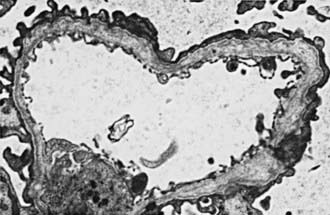

In most patients, electron microscopy reveals diffuse thickening, thinning, splitting, and layering of the glomerular and tubular basement membranes (Fig. 504-3). Ultrastructural analysis of the GBM in all genetic forms of AS may be completely normal, display nonspecific alterations, or demonstrate only uniform thinning.

Figure 504-3 Electron micrograph of a biopsy specimen from a child with Alport syndrome depicting thickening, thinning, splitting, and layering of the glomerular basement membrane (×1,650).

(From Yum M, Bergstein JM: Basement membrane nephropathy, Hum Pathol 14:996–1003, 1983.)